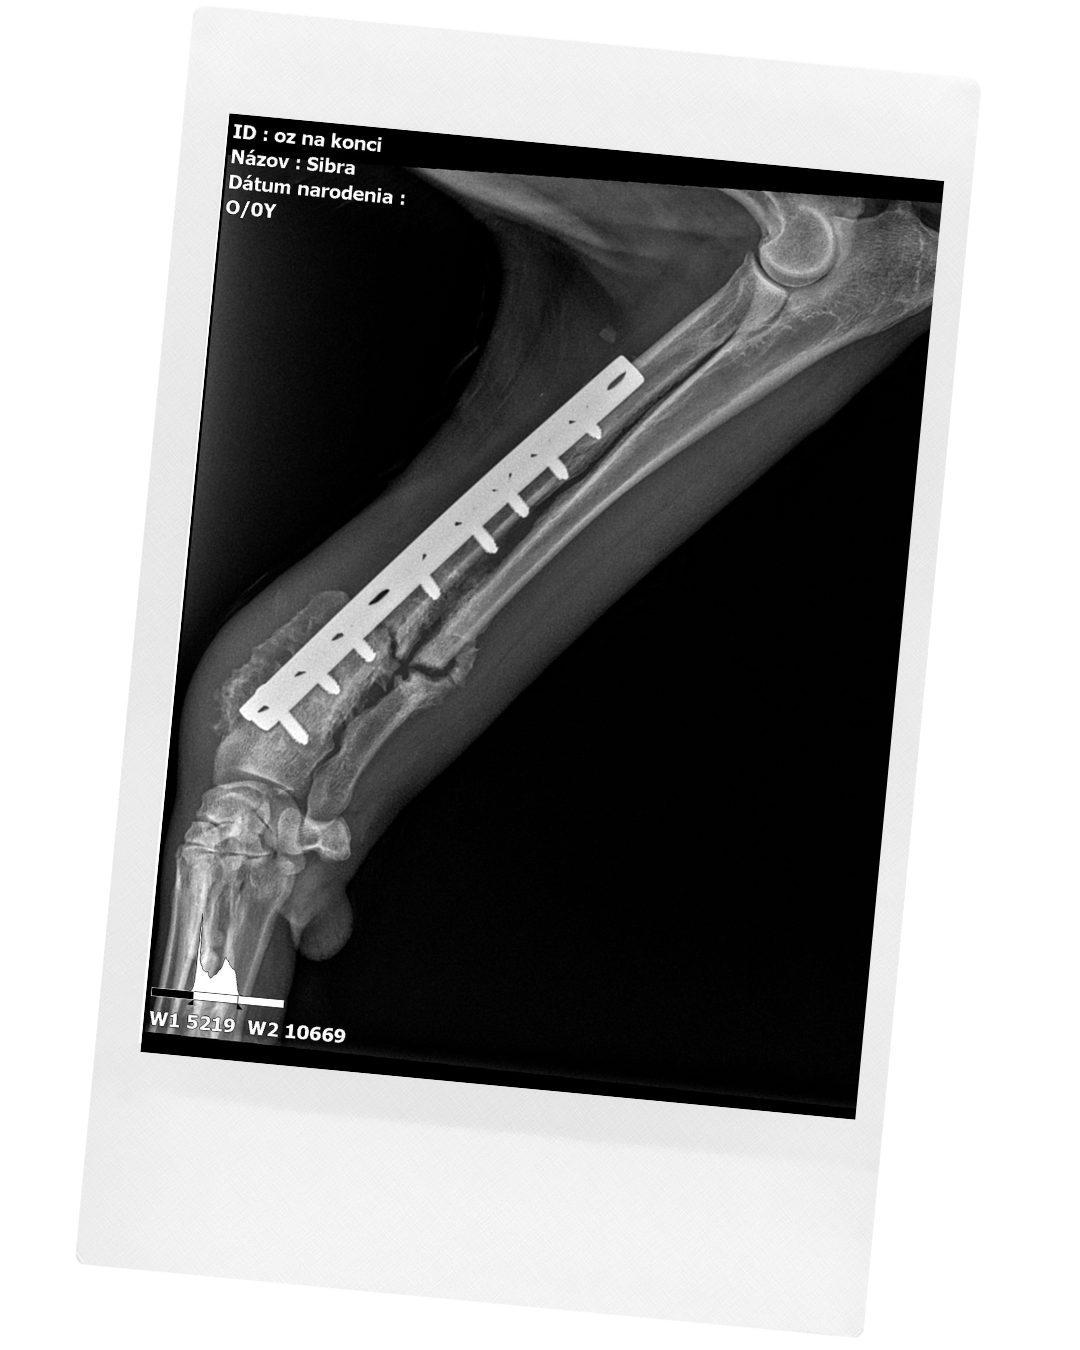

Dátum záchrany: 15.01.2025

Tieto riadky sa píšu veľmi ťažko. Sibru sa nám podarilo vyliečiť, ale nie zachrániť.

Nikto neveril, že prežije prvý týždeň a ona pritom bola bojovníčka.

Jej príbeh sa začína veľmi smutne. Túto nádhernú a majestátnu fenočku zrazilo auto. Niekoľko dní ležala s otvorenou zlomeninou pri ceste, úplne sama, kým sa nenašiel človek so srdcom na pravom mieste, ktorý ju zdvihol a odviezol na veterinárnu kliniku.

Okrem komplikovanej zlomeniny bojovala aj s babeziózou. Je to choroba prenášaná kliešťom, ktorá býva často smrteľná. Sibra sa však nevzdávala a bojovala každý deň. Babeziózu sa podarilo vyliečiť v priebehu pár dní. Po šiestich mesiacoch náročných a opakovaných operácií sa nám podarilo zahojit aj jej zranenú nožičku.

Sibra absolvovala všetky očkovania a čakala ju už len kastrácia. Osud však chcel inak. Zomrela deň pred plánovaným zákrokom. Odišla náhle, vo vysokých horúčkach, ako následok akútneho zápalu mozgových blán. Nečakane a bolestivo opustila naše životy v okamihu, kedy sme sa mi tešili, že je jej zdĺhavá liečba na úspešnom konci.

Sibra bola psia osobnosť, ktorá sa navždy zapísala do našich sŕdc.

Zomrela milovaná, obklopená svojou útulkovou rodinou, pretože pre nás nebola iba ďalším zachráneným psíkom. Bola naša rodina.